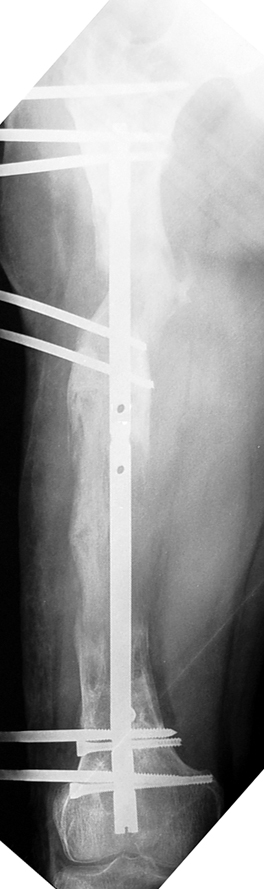

Eksternal fiksatör ile geçen süre (eksternal fiksasyon indeksi), gereken distraksiyon miktarına bağlıdır ve bu süre boyunca bazı komplikasyonlarla karşılaşılabilir. Distraksiyon dönemi sona erdikten sonra, distraksiyon süresinin iki katını aşan konsolidasyon döneminde hastalar eksternal fiksatörü zorlukla tolere edebilirler. Yeterli konsolidasyon sağlanmadan eksternal fiksatör çıkartılırsa ise kırıklar, deformite ve kısalık oluşabilir. Hastanın fiksatör ile birlikte geçirdiği sürenin azaltılması ve böylece hasta konforunun ve aktivite düzeyinin arttırılması için intramedüller çivi üzerinden uzatma yöntemi uygulanmaktadır. Bu yöntemde distraksiyon dönemi sona erdiğinde kemiğin içindeki çivi statik olarak kilitlenmekte ve eksternal fiksatör çıkartılmaktadır. Stabilizasyon intramedüller çivi tarafından sağlandıktan sonra konsolidasyon dönemi gerçekleşmektedir. Bu şekilde hem eksternal fiksatörün uzun süre kalmasından hem de erken çıkartılmasından kaynaklanan komplikasyonların önüne geçilmektedir.

Vaka 1

Vaka 2